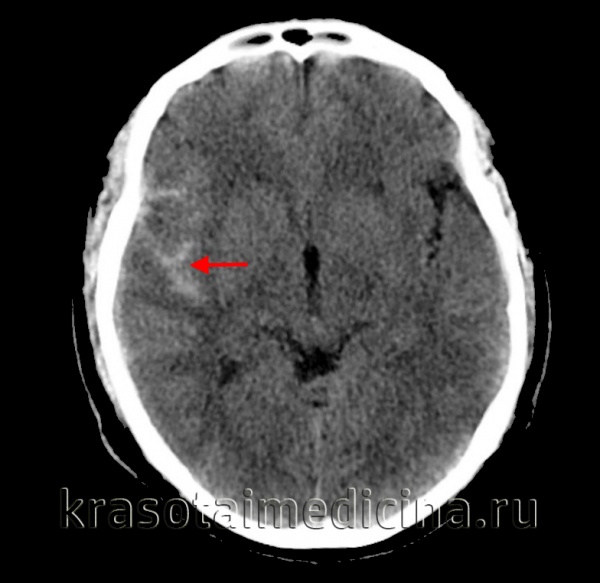

КТ головного мозга. Геморрагический инсульт, обширная интрапаренхиматозная гематома в левой гемисфере

Они позволяют определить объем и локализацию внутримозговой гематомы, степень дислокации мозга и сопутствующего отека, наличие и область распространения кровоизлияния. Желательно проведение повторных КТ-исследований, чтобы проследить эволюцию гематомы и состояние мозговой ткани в динамике.